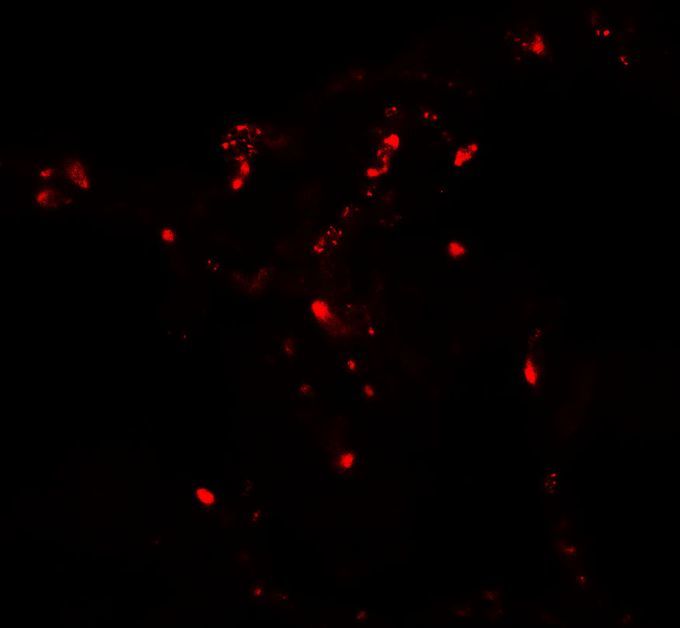

Supportive validation

- Submitted by

- GeneTex (provider)

- Main image

- Experimental details

- Immunofluorescence of ATG4C in human lung tissue with ATG4C antibody at 20 μg/ml.